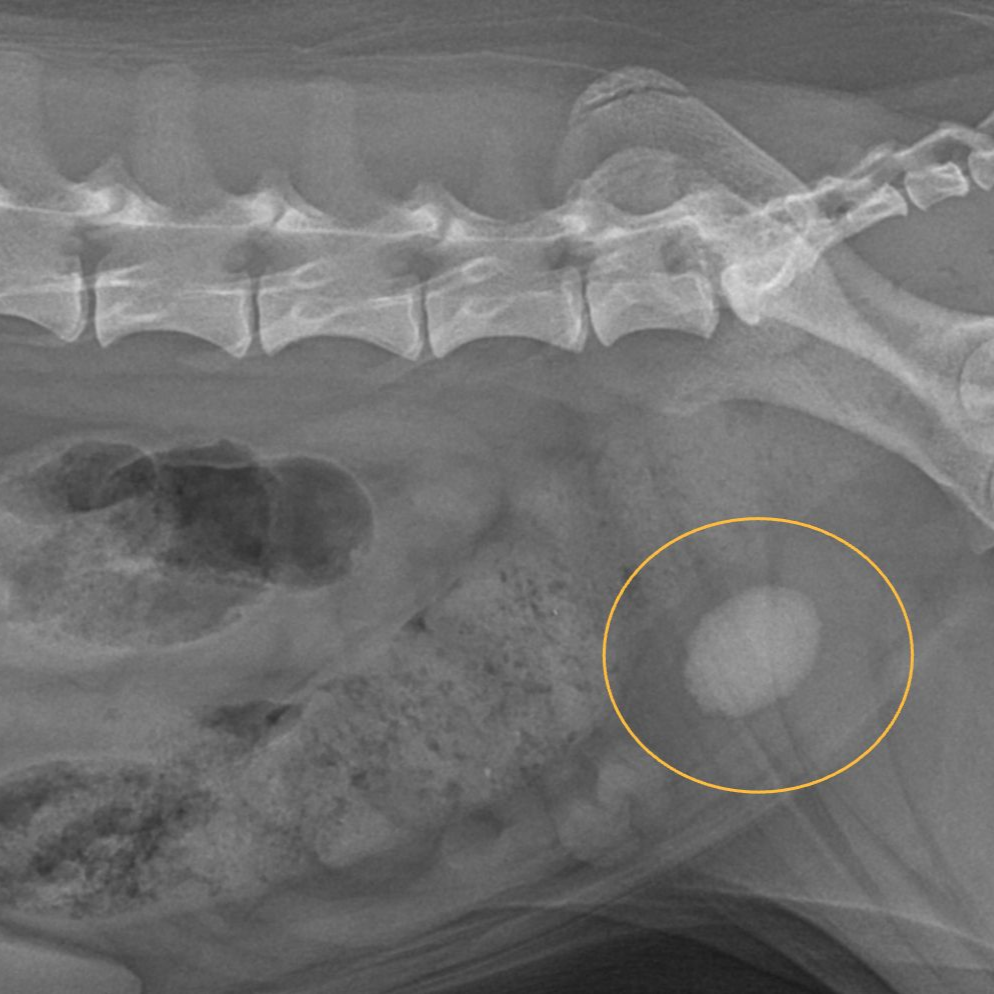

Find out about this deadly condition, how you can prevent it, and what to do if you pet develops it.